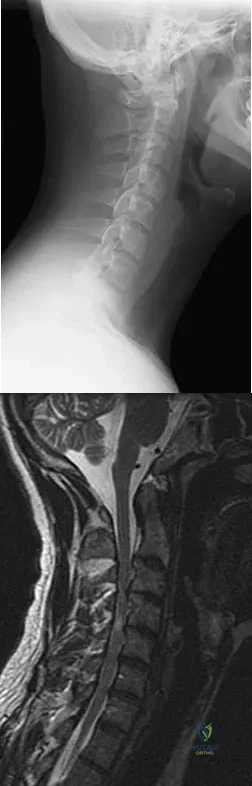

Question 37

Figures 5a and 5b show the radiograph and MRI scan of a patient who has severe mechanical neck pain but no neurologic problems. Biopsy and work-up show the lesion to be a solitary plasmacytoma. Treatment should consist of

Explanation